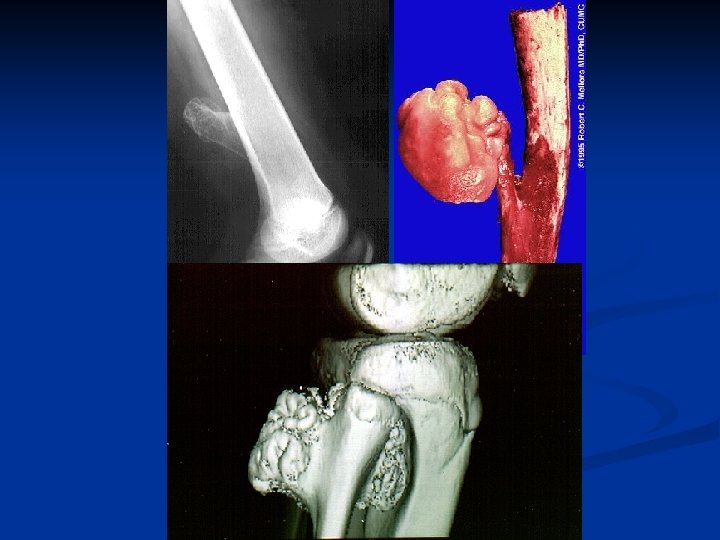

Osteochondroma n n Osteocartilaginous exostosis Most common benign tumors or tumorlike lesions of bone, In almost any bone preformed in cartilage, particularly long tubular bones, Presents as a solitary cartilage-capped bony outgrowth protruding from the bone surface near the metaphysis.

n The most common location of an osteochondroma is in the region of the knee, particularly the lower metaphysis of the femur or the upper metaphysis of the tibia. n occasionally in a flat bone n n such as a rib, clavicle, ilium, or vertebra.

n Pathology n A sessile or stalked, cartilage-capped, bony protusion which extends from the metaphysial region n Microscopically n bony protusion n a cap of mature cartilage

- bony protusion - a cap of mature cartilage